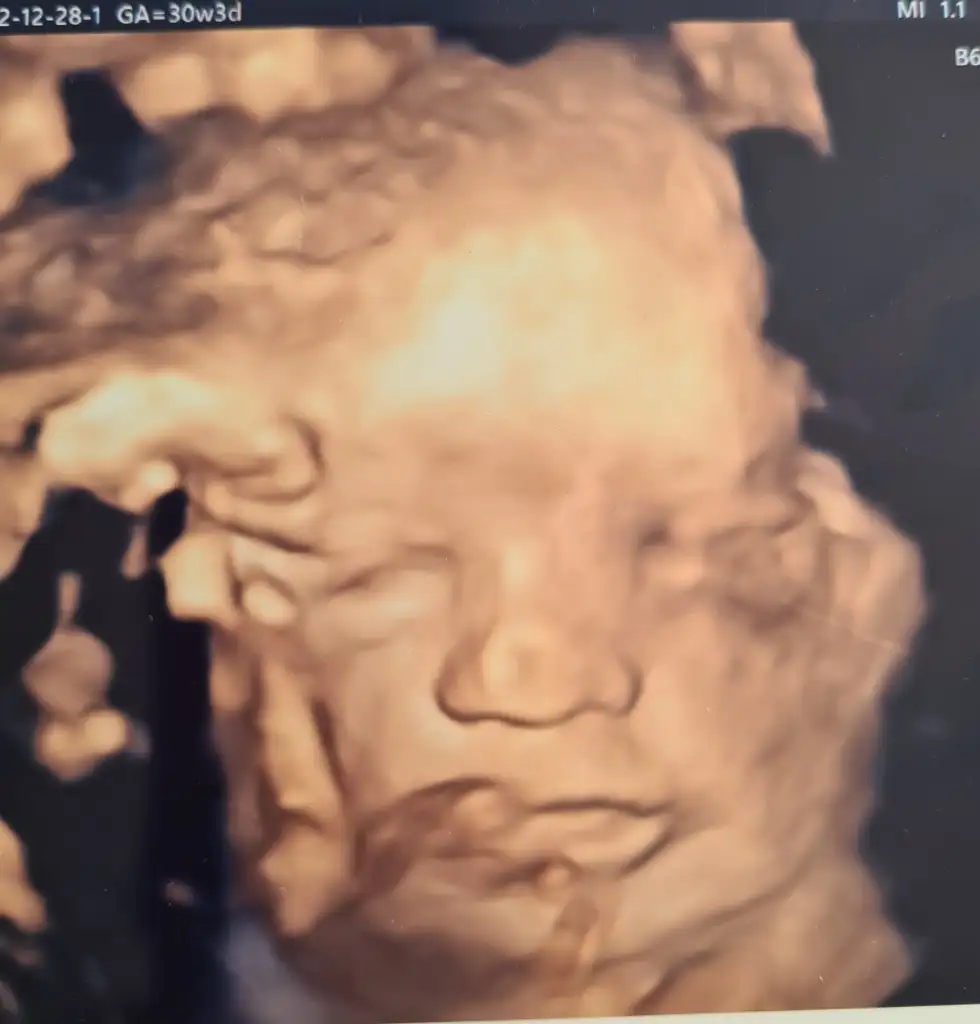

Ben de dün kontrole gittim bu arada 🥰 Bebişim 30 haftalık 1.600 gr ve 41 cm. Haftasıyla uyumlu🙏🏻 İyi de kilo almış maşallah 🧿 3 haftada 600 gr almış şükür. Minnakım da burada işte 🥰 Yanaklar dolmuş maşallah 🧿🙏🏻